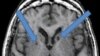

Kabar kematian orang-orang yang kita cintai meningkatkan risiko serangan jantung seseorang (foto: ilustrasi).